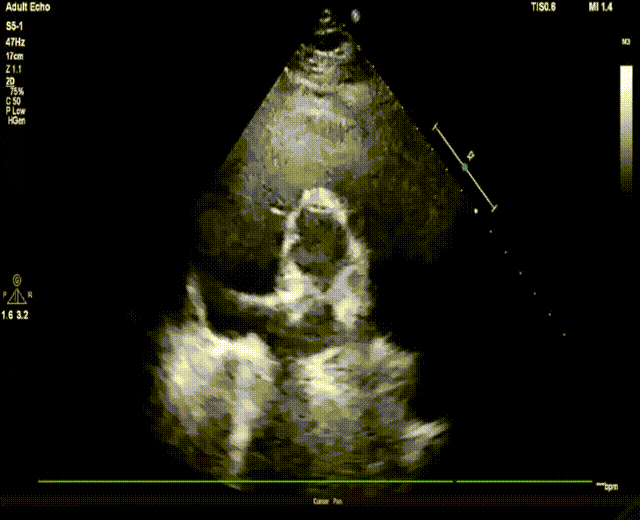

后在TTE指导下,术者按照标准操作流程先释放封堵器左盘,牵拉成型线,使封堵器左盘由纺锤形变成“圆盘形”;后释放右盘,经二次成型,使封堵器骑跨缺损两侧,紧贴室间隔,锁定成型线。

上:左盘释放成型;下:右盘释放成型、双盘骑跨缺损两侧

经牵拉测试,封堵器位置形态稳定,对瓣膜功能无影响,故完全释放封堵器。

复查超声及造影提示封堵器位置形态稳定,无残余分流,手术圆满成功!

完全释放封堵器

术后超声